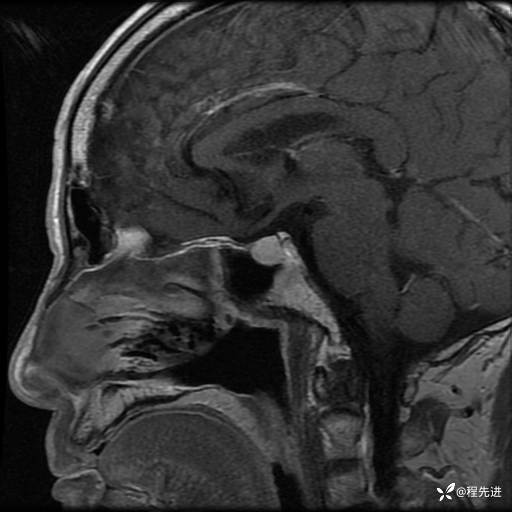

MRI平扫+增强:

T2: